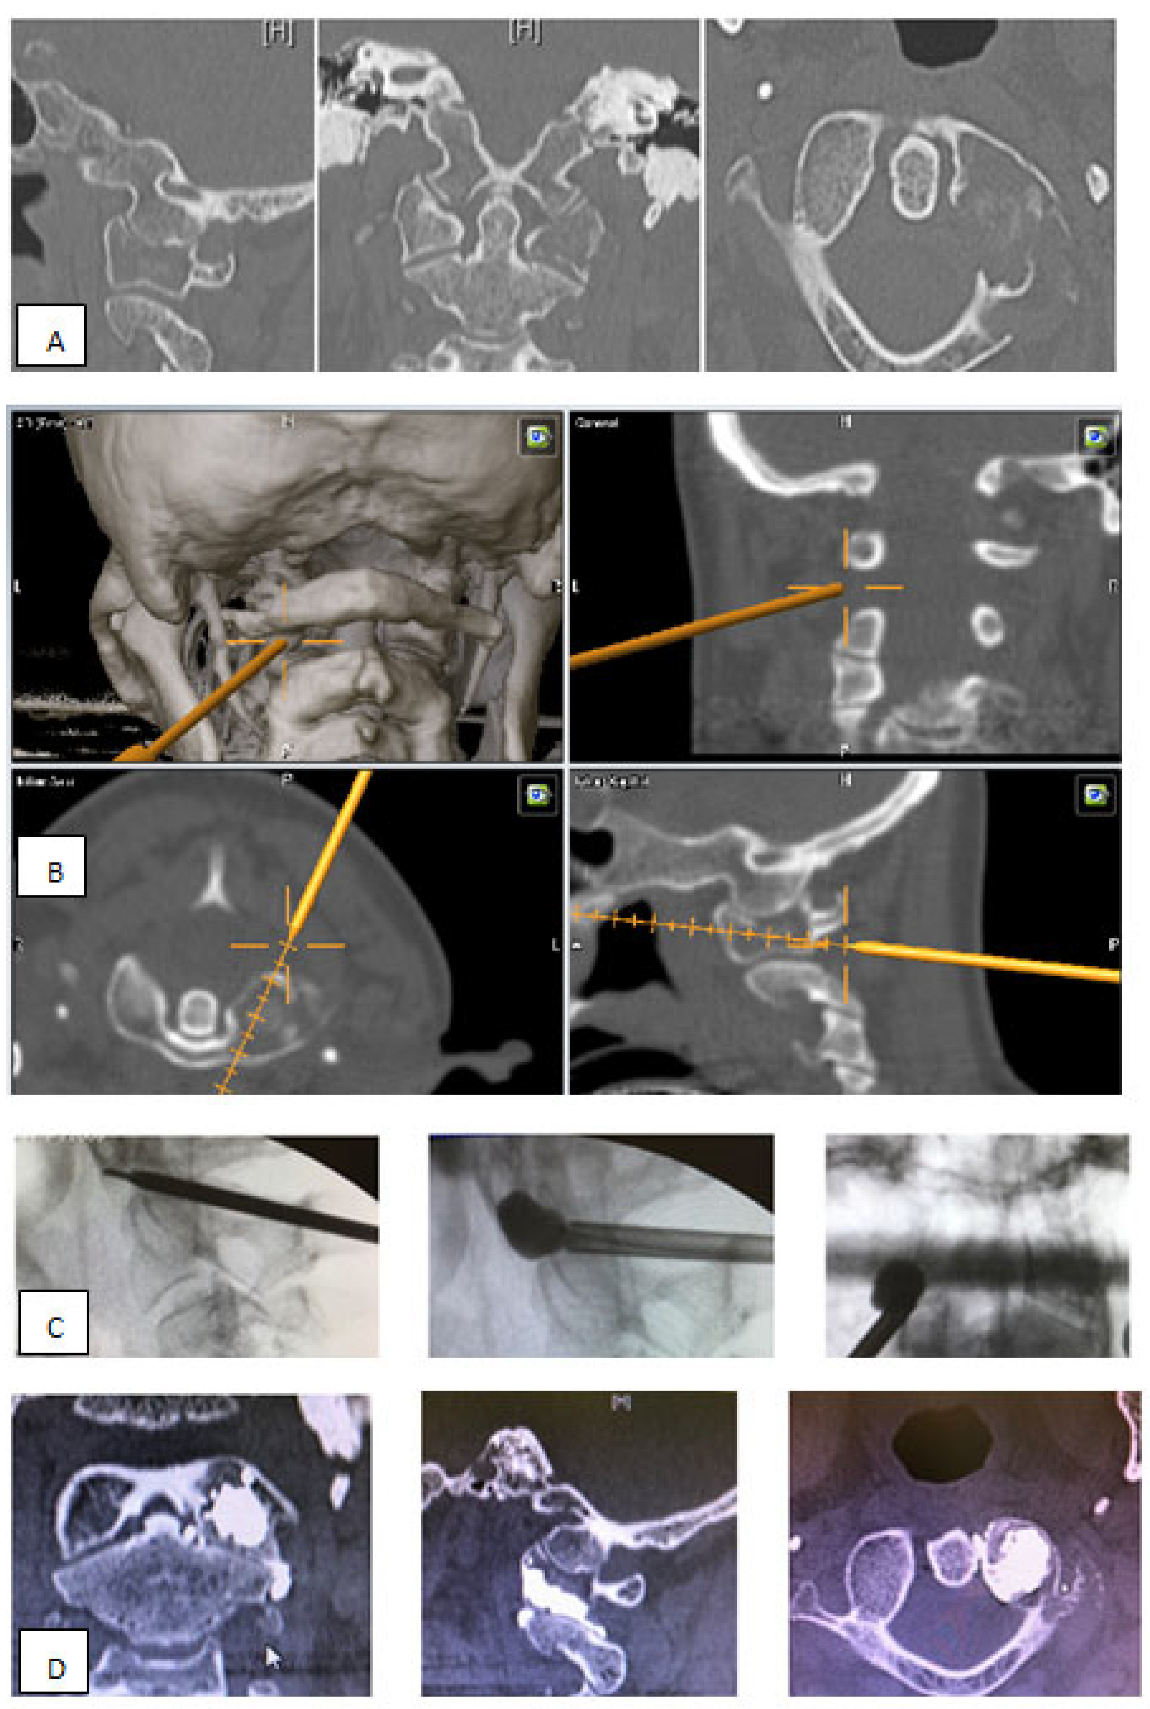

- Posterior percutaneous kyphoplasty for cervical spine metastases (Figure 2); case of C2-C3 kyphoplasty.

- Metastatic lesions of C1 are extremely rare, and their treatment by percutaneous cement augmentation is considered to be a technically challenging procedure due to complex anatomy. We also performed percutaneous kyphoplasty in a painful osteolytic lesion located on the left lateral mass of C1 through a posterolateral approach using a 3D CT scan intra-operative navigation system and fluoroscopy (Figure 3) [22].